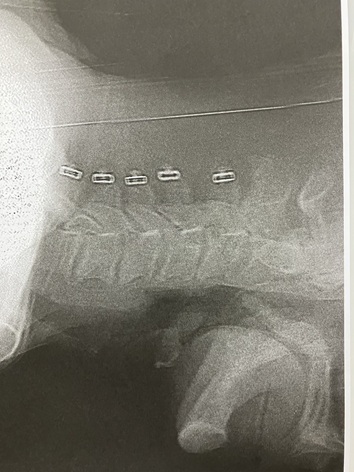

æ“V«“I‚ÈœŠi‚ª–â‘è‚©‚ÆlŽ@‚µ‚Ä‚µ‚Ü‚¤’ö‚̘c‚Ý‚ª‹­‚­AXü‚ÅŠm”FB

9‚©ŒŽŒãAÇóÁޏ‚É‚ÄÄ“xXü‚ÅŠm”FB